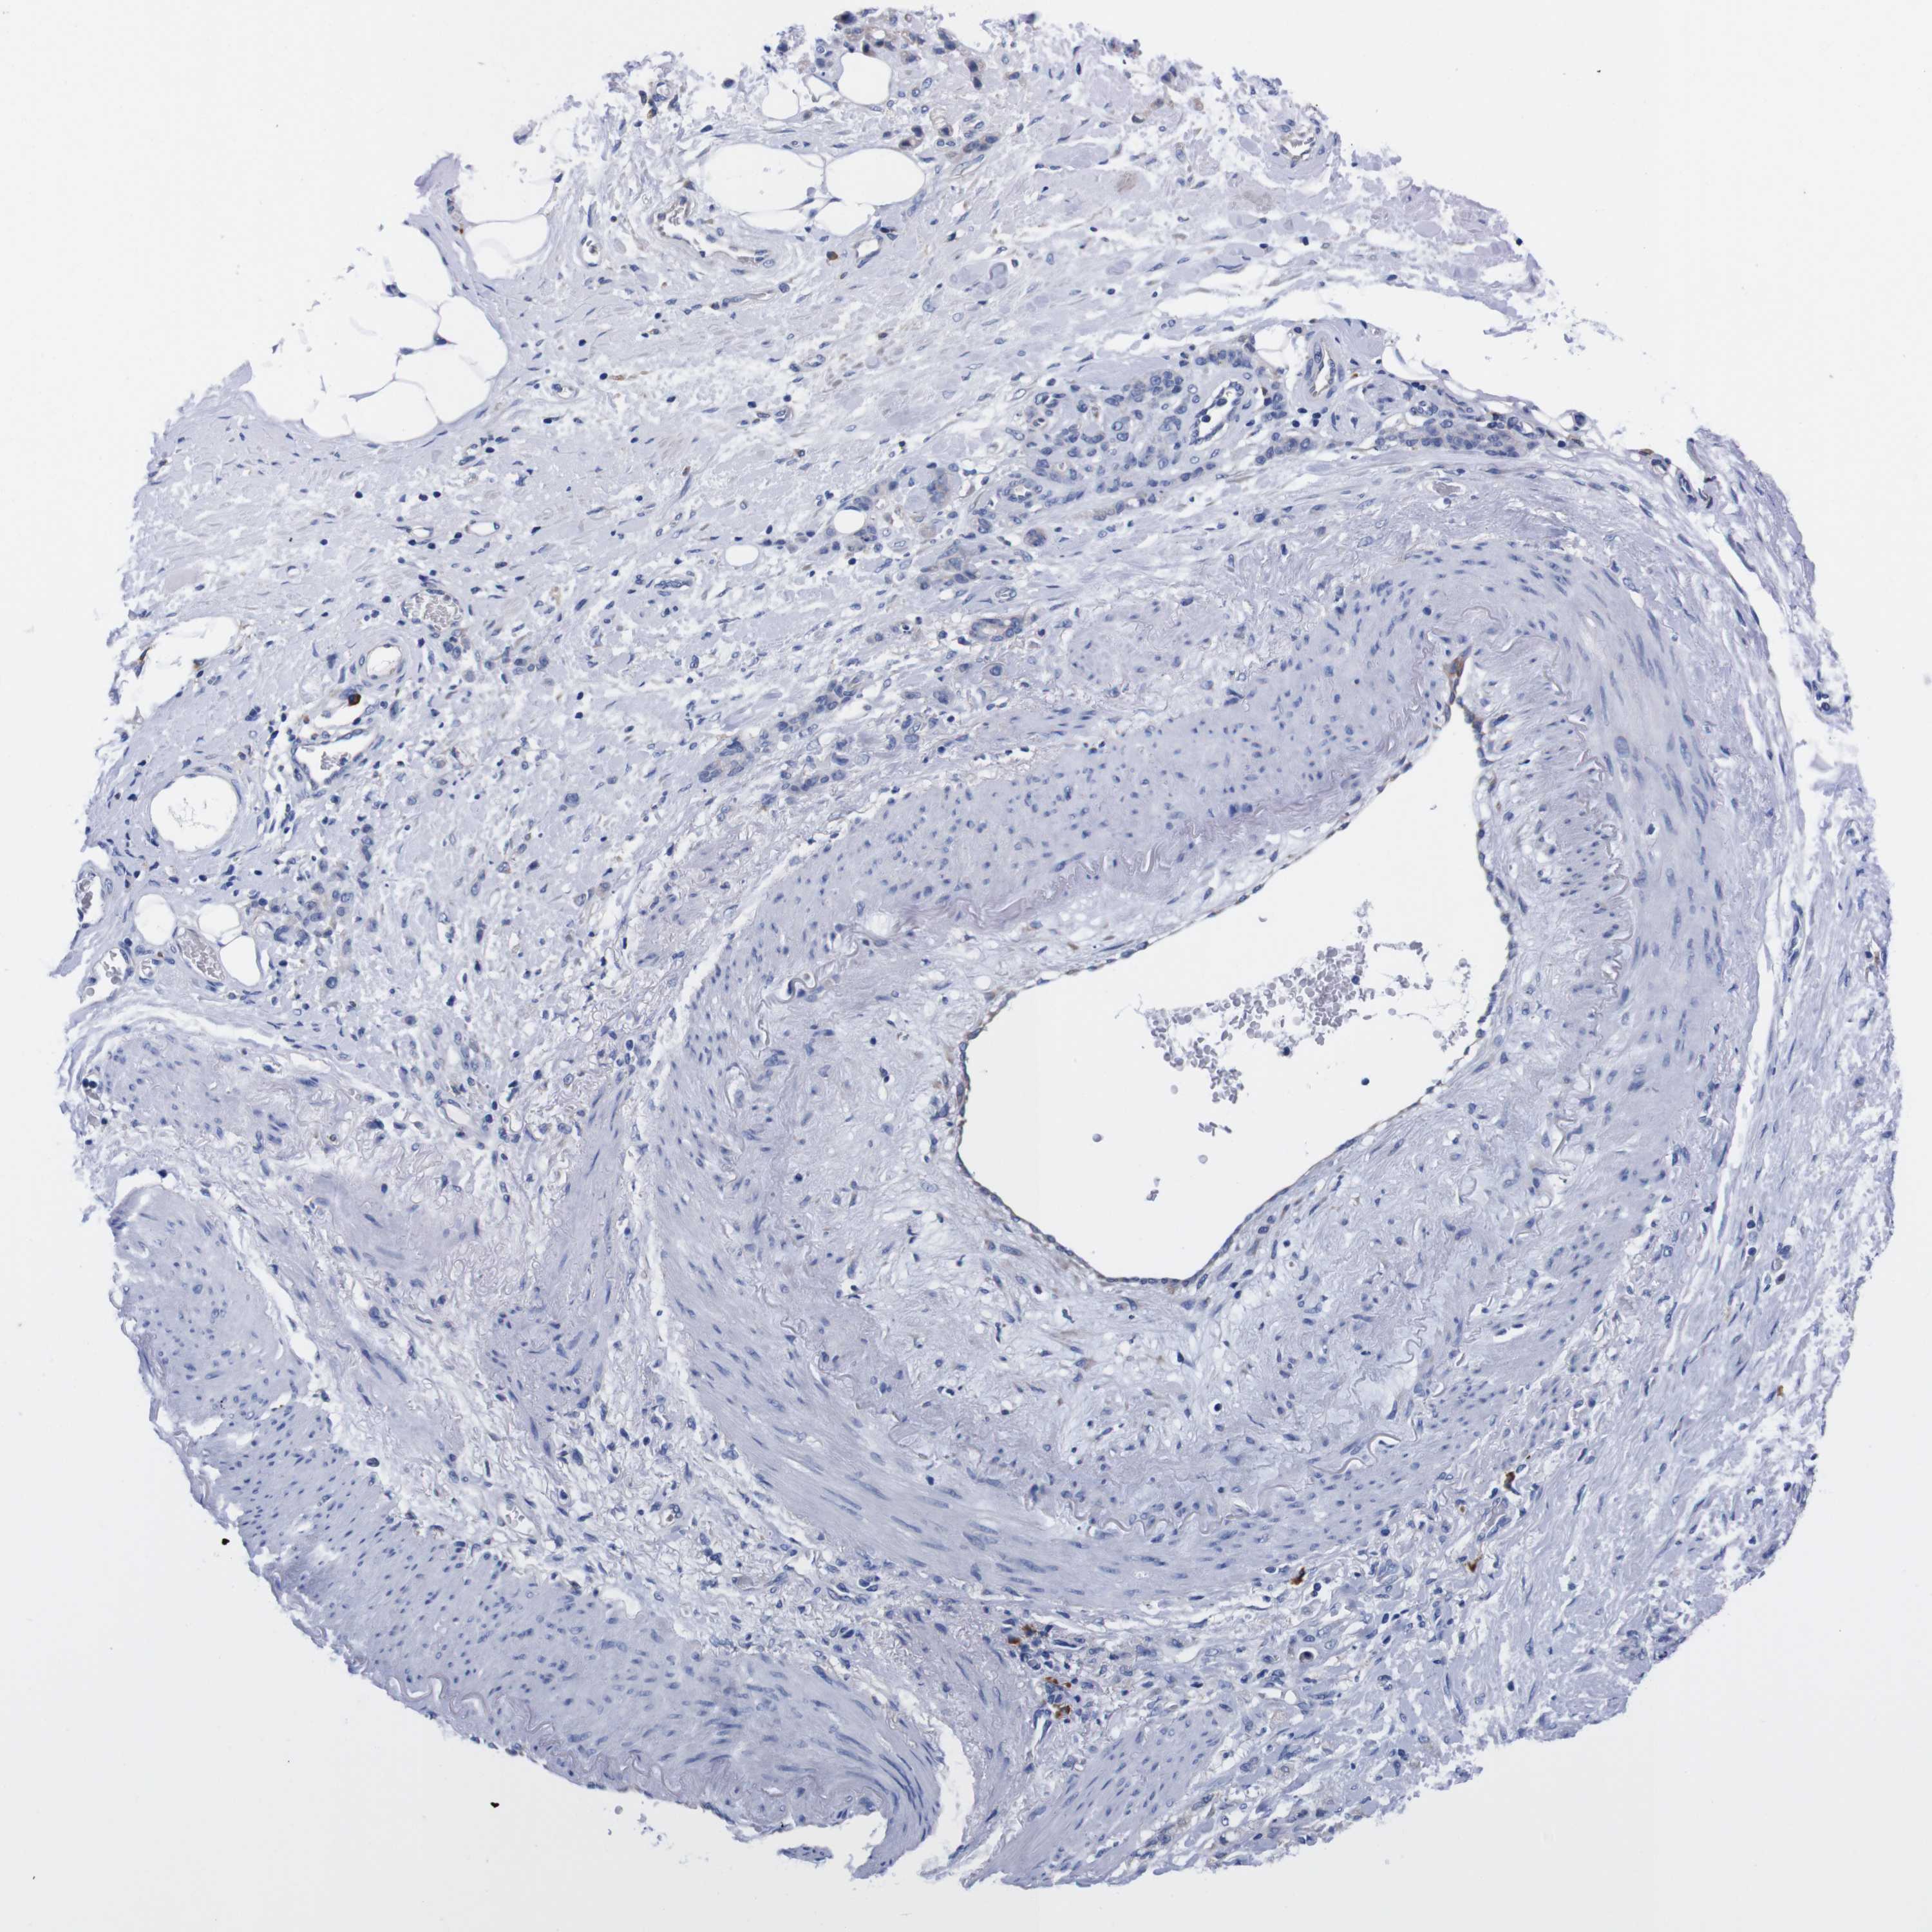

STOMACH CANCER - Protein expressioni

A mouse-over function shows sample information and annotation data. Click on an image to view it in a full screen mode. Samples can be filtered based on level of antibody staining by selecting one or several of the following categories: high, medium, low and not detected. The assay and annotation is described here.

Antibody stainingi

Antibody staining in the annotated cell types in the current human tissue is reported as not detected, low, medium, or high, based on conventional immunohistochemistry profiling in selected tissues. This score is based on the combination of the staining intensity and fraction of stained cells.

Each image is clickable and will lead to virtual microscopy that enables deeper exploration of all samples and also displays staining intensity scores, fraction scores and subcellular localization as well as patient and tissue information for each sample.

Antibody HPA013994

Antibody HPA013995

Staining

High

Medium

Low

Not detected

Intensity

Strong

Moderate

Weak

Negative

Quantity

>75%

75%-25%

<25%

None

Location

Nuclear

Cytoplasmic/membranous

Cytoplasmic/membranous,nuclear

Adenocarcinoma, NOS

Adenocarcinoma, High grade